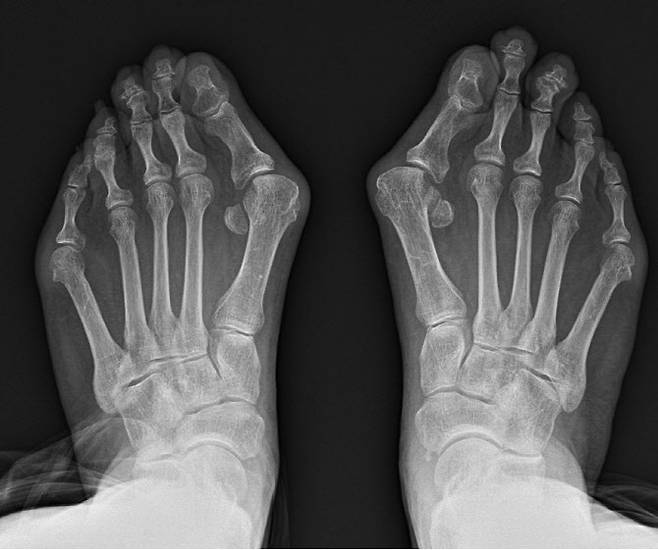

그 대표적인 예로 무지외반증을 꼽을 수 있다. 무지외반증 이란 엄지발가락이 새끼발가락 방향으로 휘며 엄지발가락이 시작되는 관절의 뼈가 돌출되는 질환이다.

유전적 요인과 함께 폭이 좁은 신발을 오래 신는 등 후천적인 요인이 영향을 미친다. 특히 최근 고령화가 가속화되며 환자가 증가하고 있는데, 건강보험심사평가원 의료정보 공개에 따르면 지난 3년간 약 18만 3000여명이 치료를 위해 병원을 찾았다.

박의현 연세건우병원 병원장은 “무지외반증은 필연적으로 보행의 불균형을 유발한다. 정상인은 보행 시 엄지발가락에 체중의 약 60%가 실리지만 무지외반증 환자는 엄지발가락이 휘어져 있어서 그 반대로 발의 중지나 약지에 몸무게가 쏠려 정상적인 보행이 불가능해진다”고 설명했다.

이에 무지외반증 환자는 무의식적으로 엄지발가락에 체중을 싣지 않고 걷게 돼 필연적으로 발목·무릎·허리에 불필요한 스트레스가 발생, 관절·척추 질환으로 이어질 수 있다. 실제 여성 무릎관절염 환자 중 무지외반증이 동반은 비교적 흔한 편이다.